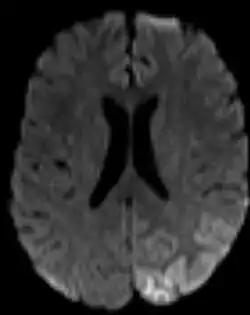

Lobe pariétal en gauche en situation d'hypoperfusion

Ce mot désigne le plus souvent l'ischémie cérébrale, la baisse de la vascularisation d'une région du cerveau (qui semble être à long terme un facteur de démence et de maladie d'Alzheimer[1])

Dans un diagnostic, le mot est souvent associé à une description géographique de la partie de l'organe touché, par exemple une « hypoperfusion pariéto-temporale droite » désignera un débit sanguin diminué dans la partie du cerveau située à hauteur du pariétal (en haut), à droite, et au niveau des tempes.